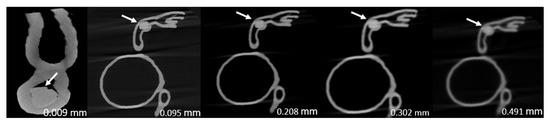

- Model 2: >90% and 70% stenosis in LAD and left circumflex (LCx), respectively.

| 2 | 80.0 ± 0.044 | 97.2 ± 0.025 | 97.8 ± 0.022 | 96.4 ± 0.012 | 96.4 ± 0.010 | <0.0005 |

| 2 | 60.0 ± 0.031 | 70.0 ± 0.003 | 71.7 ± 0.022 | 77.8 ± 0.011 | 84.8 ± 0.008 | <0.0005 |